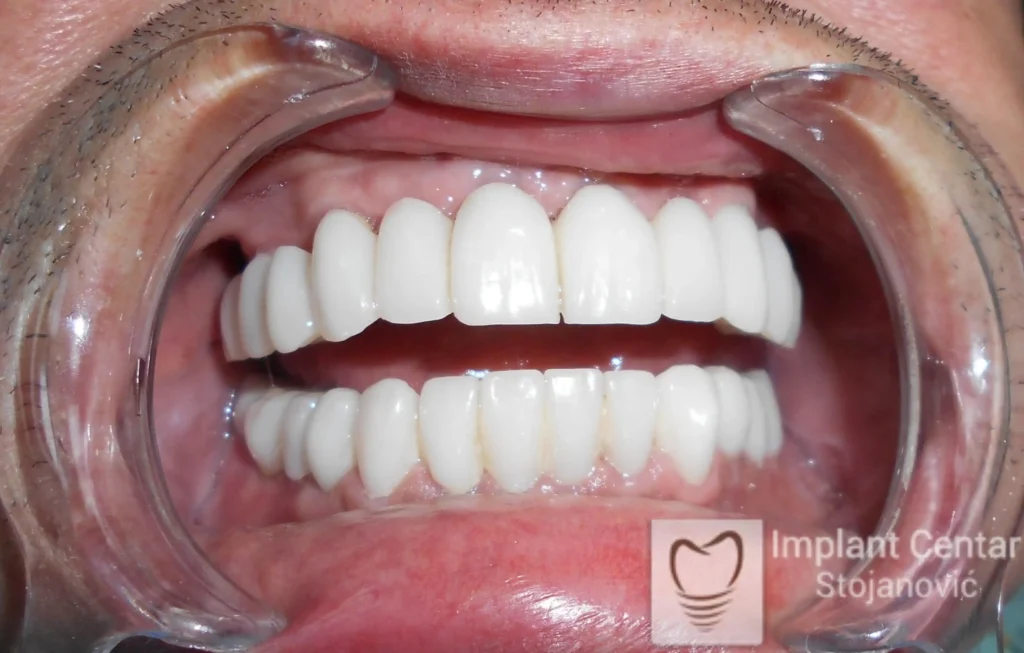

Na slikama 5. i 6. prikazan je izgled definitivnih cirkonijum-keramičkih mostova na implantatima.

Pacijent je izuzetno zadovoljan — kako estetikom novog osmeha, tako i funkcijom, jer ponovo može bez problema da jede i da se smeje.